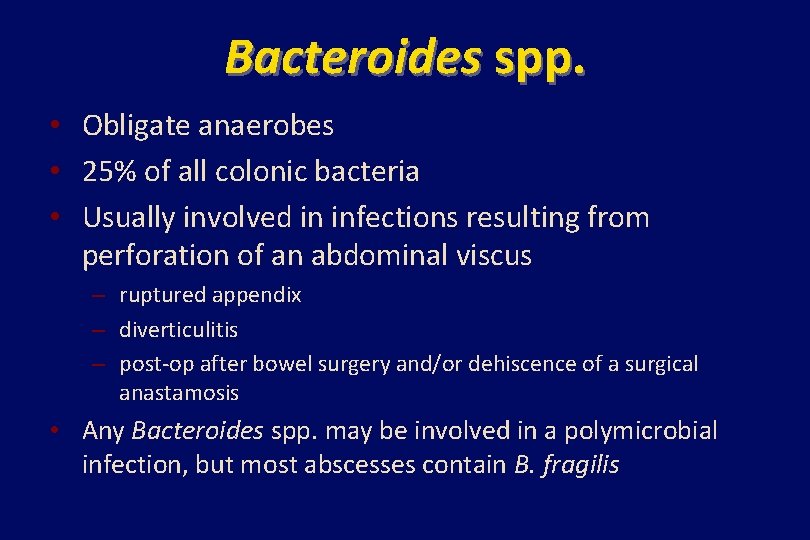

Bacteroides spp. • Obligate anaerobes • 25% of all colonic bacteria • Usually involved in infections resulting from perforation of an abdominal viscus – ruptured appendix – diverticulitis – post-op after bowel surgery and/or dehiscence of a surgical anastamosis • Any Bacteroides spp. may be involved in a polymicrobial infection, but most abscesses contain B. fragilis